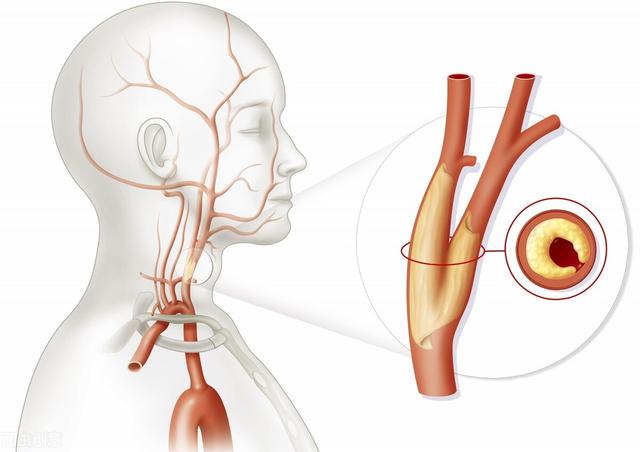

血管因子(最も一般的):脳へつながる血管や脳内の血管の流れが悪いなど。 主な原因は動脈硬化と頚椎症の2つ。

- a. 動脈硬化:これが最も一般的な原因である。脳につながる動脈の開存性と脳内の動脈の開存性の両方に影響を及ぼす。頸動脈は脳に血液を供給する最も重要な動脈のひとつである。アテローム性動脈硬化症は頸動脈にプラークを形成する。アテローム性動脈硬化症は頸動脈にプラークの形成をもたらし、プラークの形成は血管の内腔の狭窄をもたらし、内腔の狭窄は脳への血流不足をもたらす。

動脈硬化は全身の動脈に影響を及ぼすが、脳内の動脈は免れない。その結果、脳への血流が悪くなり、脳内の血流も悪くなる。二重の影響が脳への血液供給に影響し、脳への血液供給が不足する。動脈硬化は高齢者の血液供給不足の最も重要な原因である。

血管が原因。血管壁の損傷、内腔の狭窄、血管攣縮などである。脳動脈硬化、壁に硬化したプラークの形成、内腔の狭小化、菲薄化、血管抵抗の増大による血流量の減少、特に脳を長時間にわたって酷使し続けた後に、脳血液の供給と相対的に起こることが多い。

頸動脈などのプラークは、血流が通過するにつれて小さくなるため、脳への血液供給不足につながる。この病変は超音波検査で発見することができ、一般的な治療方針は、血圧をコントロールし、血中脂質を下げることで、プラークが大きくなるのを防ぎ、腫瘍性プラークを予防することを目指すが、プラークを除去することはできない。プラークがあまりに大きく、脳への血液供給に深刻な影響を及ぼすような場合には、外科的切除も選択肢となる。